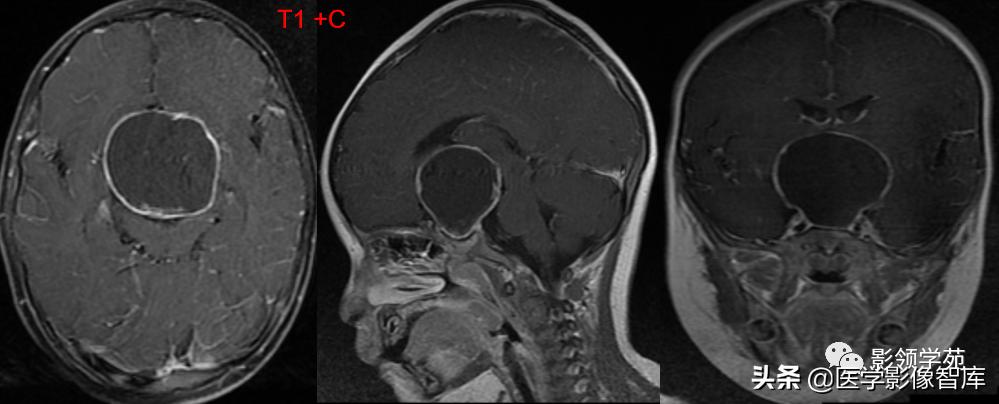

女 72岁,发现糖尿病3年余

鞍上区见一团块状稍高密度影,边界尚清,密度均匀。

鞍上右上方见一类椭圆形流空影。

病灶明显强化(瘤内血栓未强化),边界清楚,与右侧颈内动脉海绵段分界不清。垂体大小、形态未见异常。